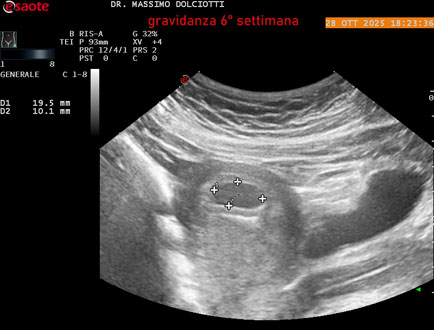

Età Paziente: F 35 anni

Motivazione dell'esame: amenorrea.

Commento all'esame: le immagini ed il video documentano in utero il sacco gestazionale, il sacco vitellino e presenza di embrione delle dimensioni di 4,7 mm (CRL), con iniziale attività cardiaca, documentata nel video.

Conclusioni: gravidanza alla 6° settimana di gestazione (pregnancy to the 6th week of gestation).